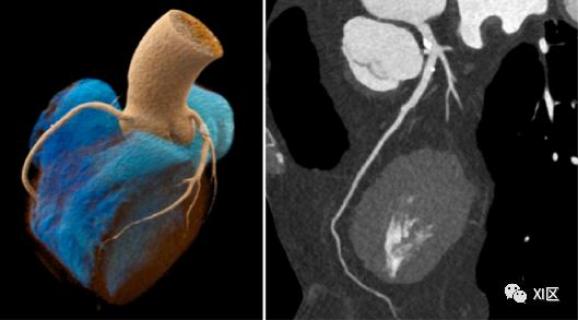

多能量数据(“颜色信息”)在每次扫描中都可用。这些额外的多参数和内在一致的数据可能有助于放射科医生在未来改进他们的诊断。即使在今天,双能应用也有助于选择最合适的治疗方法,但并非总是适用于每种情况。冠状动脉造影剂和钙化的清晰分离是“彩色数据”可以满足的许多挑战性任务之一(图17)。

图17 冠状动脉多能量成像具有最高的空间分辨率和时间分辨率。即使在钙负荷较高的情况下,对CAD患者的信心评估也是如此。在这些单能65keV图像中,冠状动脉中的钙化明显与血管腔分离。由此可见,光子计数探测器在CT扫描的几乎每一个临床应用中都是非常有前途的。相信随着商用系统进入临床,更多的临床应用会被挖掘出来。医学X射线成像将从已知的灰度图像发展为高分辨率彩色图像,就像我们在过去几年中观察到的相机和胶片技术的发展一样。这项技术的真正潜力将在未来的研究中进行调查,可能不限于特殊情况。因此,这有助于使全球所有人类的生活更加健康。